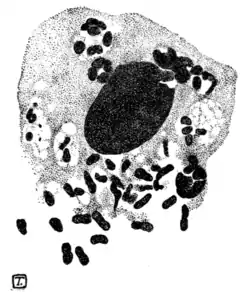

Donovan described certain parasitic elements in scrapings from the deeper parts of the Madras form of these sores. The parasite (Fig. 93) is like a short bacillus with rounded ends, measuring 2 μ by 1 μ. It occurs in mononuclear cells and in great profusion. The parasites are sometimes scattered irregularly through the protoplasm of the affected cells; more often they are arranged in little round clusters of eight or ten. Recently de Souza Araujo and others in Brazil have confirmed and extended Donovan's discovery. The Calymmatobacterium granulomatis, as they term the germ, is capsulated, non-motile, Gram-negative, non-spore-forming, does not liquefy gelatin nor coagulate milk. Under cultivation it is polymorphic, occurring as cocci, diplococci, bacilli, diplobacilli, and filaments, all forms possessing a

Fig. 93.—Parasitic elements in ulcerating granuloma of pudenda.

mucous capsule. It retains its virulence in experimental animals as far at least as the hundredth sub-culture on gelatin. In sections of the affected tissues the bacteria are seen to lie both inside and between the cells as capsulated cocci or diplococci, in chains or in zooglœa masses.